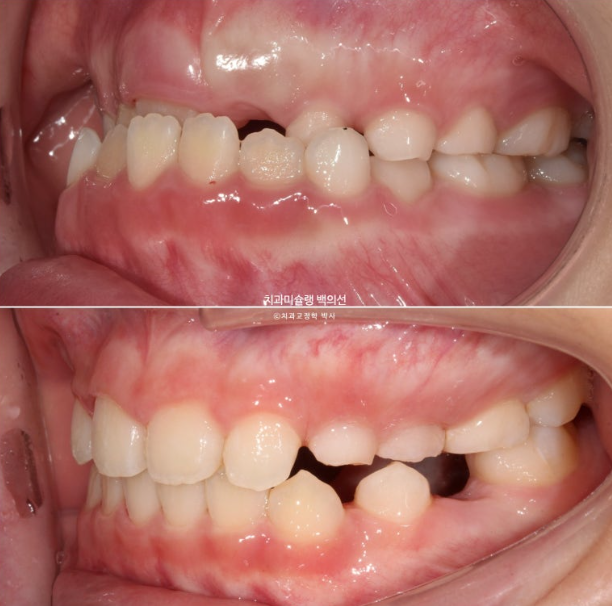

하지만 여전히 어금니 반대교합이 남아있습니다.

유치 송곳니도 여전히 거꾸로 물려 교합간섭이 남아있습니다.

어금니 반대교합은 상악 악궁이 좁아서 생기는 문제입니다.

즉 악궁확장이 필요하고 인비절라인 퍼스트로 악궁확장을 동반하여 MA (mandible advance, 하악전진기능) 기능을 이용한 비대칭 치료가 필요합니다.

드디어 앞니 4개가 나왔으며 반대교합 치료 결과는 잘 유지되고 있습니다.

어금니 반대교합의 원인은 좁은 상악 악궁에 있습니다.

이제 인비절라인퍼스트 치료로 악궁확장, 앞니배열 등을 먼저 진행하여 교합간섭 해소를 도모합니다.